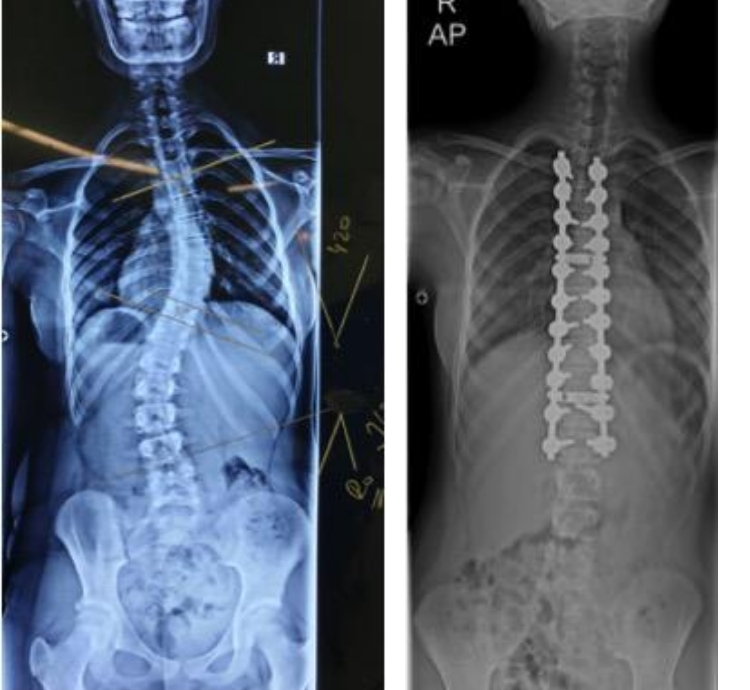

Skolyoz hastalığı, halk arasında omurga eğikliği olarak da bilinir. Omurganın sağa ya da sola doğru normal dışı eğikliği demektir.

Skolyoz hastalığı gebelikte bir belirleyici unsur değildir. Yani hamilelikte bir sıkıntı yaratmaz. Hastanın gebe kalmasında ve gebelik sürecinde herhangi bir soruna yol açmaz. Gebe kadınlarda kemik gelişimi tamamlandığı için hastalığın ilerlemesi de genel olarak başa gelen bir durum değildir. Hamilelik sürecinde diğer gebelere göre bel ağrısını daha fazla yaşamazlar. Yani gebelik sürecinde bu rahatsızlık ekstra bir dezavantaj yaratmaz. Sağlıklı bir bireyden hiçbir fark olmaksızın bu süreci tamamlayabilirler.

Genel olarak hamilelik sürecini çok fazla etkilemeyen bu rahatsızlık, doğumda da belirleyici değildir. Skolyozlu gebeler de normal doğum yapabilirler. Omurilik hastalığı olmayan diğer kadınlardan farksız şekilde gebelik geçirirler. Ancak omurgadaki eğiklik yüksek açılı ise, hastada aynı zamanda kalp, akciğer hastalıkları da varsa doğum sezaryen olarak yapılır. Bu anne ve bebek sağlığı için zorunlu bir durumdur. Doğumdan önce annenin mutlaka muayene olması ve bu rahatsızlıklarına göre bir doğum yolu izlenmesi gereklidir.